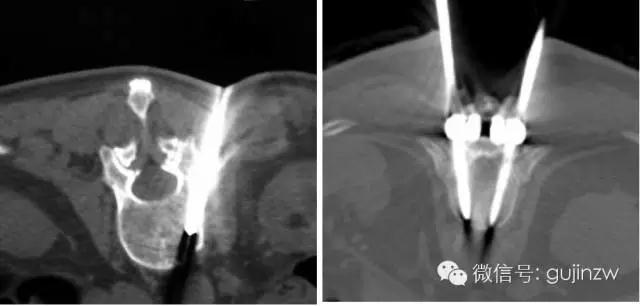

确定进钉点后,先咬除进钉点处皮质骨,开口器开口,恒力持稳探路器缓慢进入,在松质骨内应阻力不大且均匀,如有大的阻力,可能遇到骨皮质,应拔出探路器,将咬除的棘突剔净、修剪成骨条后填入钉道,再次用探路器,则易控制方向,避免滑入原钉道。进钉前一定要用探针探测钉道四壁有明显骨性感,证实钉道在椎弓根内,方可缓慢拧入螺钉。

3、确定好大致方向后,适当用力谨慎开路,尖端圆钝探针在进针过程中不应该遭遇明显阻力不能有“落空”感或阻力骤强,在最初的5~15mm遭遇阻力,应及时调整进针点和角度。如遇到坚强阻力,建议先退出,重新选择方向进入,务必顺应椎弓根方向,椎弓根内部是松质骨,外侧是皮质骨,相对可以自动导向,前提是入点准确并适当扩大;向中线倾斜10—15°,注意与椎体上缘平面平行,掌握大概深度3cm。手感很重要。

4、用椎弓根探子探四壁很管理重要,特别是内、下、底壁。